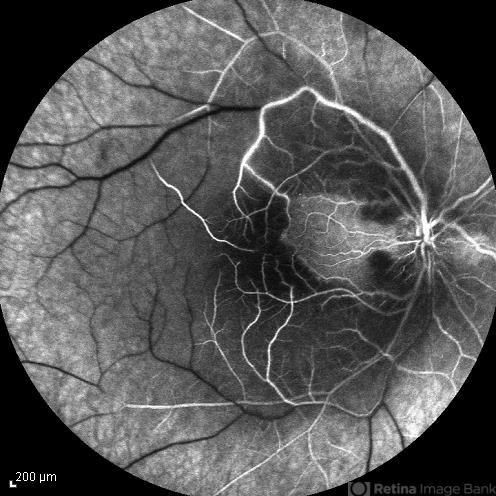

- central retinal artery occlusion (CRAO), cilioretinal sparing

- Late phase FA image of the right eye of a 34-year-old man with sudden drop of vision due to CRAO. The macula is involved despite cilioretinal artery sparing .